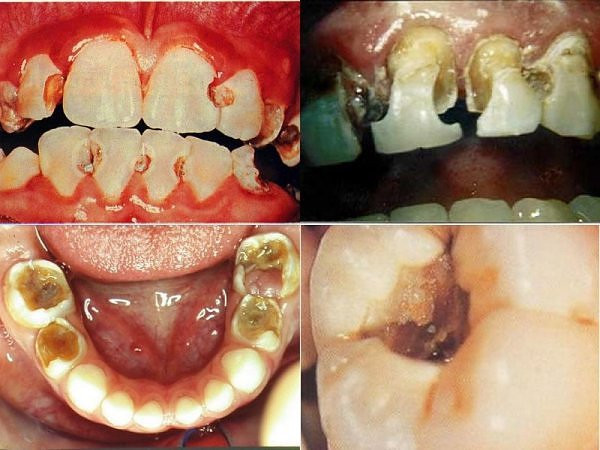

Người tiêu thụ đường tự do trên 10% tổng số nhu cầu năng lượng hay ăn các món có đường tự do trên bốn lần trong ngày sẽ tăng nguy cơ bị sâu răng. Đường tự do gồm tất cả đường đơn, đường đôi, ví dụ glucose, sucrose (đường mía), fructose (đường trái cây), dextrose...

| Sâu răng (Ảnh minh họa/ Nguồn: Internet) |

Những loại đường này có thể xuất phát từ tự nhiên như đường mía, đường trái cây, cũng có thể là đường công nghiệp thêm vào bánh, kẹo, kem. Các loại thực phẩm dễ gây sâu răng bao gồm kẹo, nước ngọt, bánh ngọt, bánh snack, bánh bông lan, trái cây ngọt, chè các loại, kem... Tinh bột trong cơm, khoai, bánh mì không tăng nguy cơ sâu răng.

Bên cạnh sâu răng, mòn men răng cũng liên quan đến dinh dưỡng. Các nhà khoa học thấy rằng thực phẩm mang tính acid, ví dụ như trong nước ngọt và các loại nước trái cây, có thể làm giảm độ pH của vùng men răng làm mòn dần lớp men răng (men răng chịu được độ pH tối ưu ở mức 5.5). Mòn men răng kéo dài làm giảm kích thước răng và nặng là phá hủy răng.